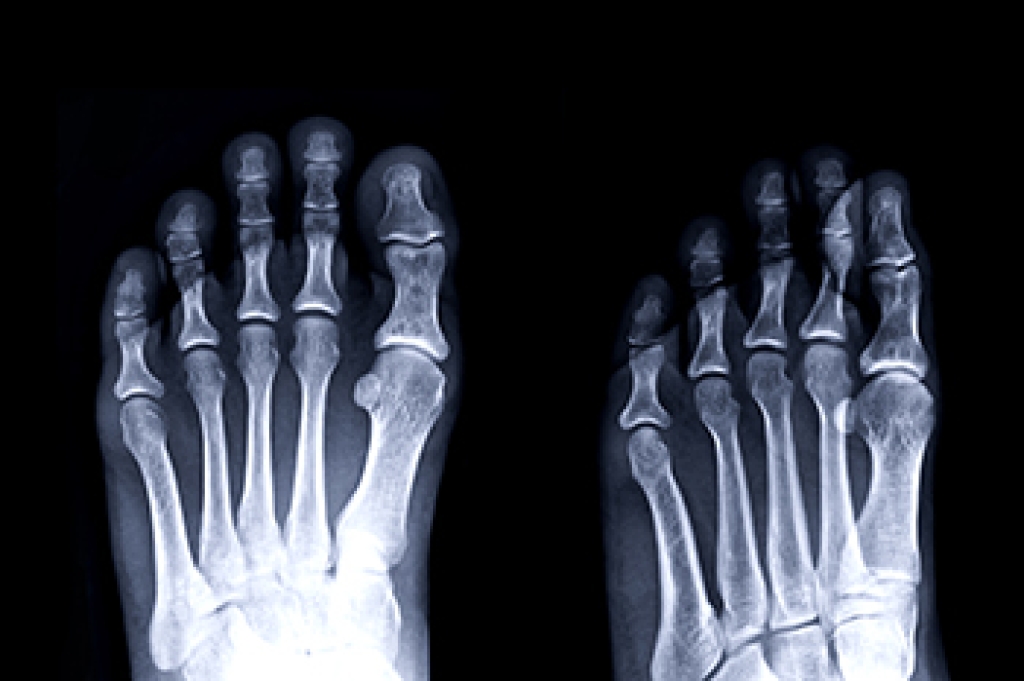

To figure out the cause of foot pain, podiatrists utilize several different methods. This can range from simple visual inspections and sensation tests to X-rays and MRI scans. Prior medical history, family medical history, and any recent physical traumatic events will all be taken into consideration for a proper diagnosis.